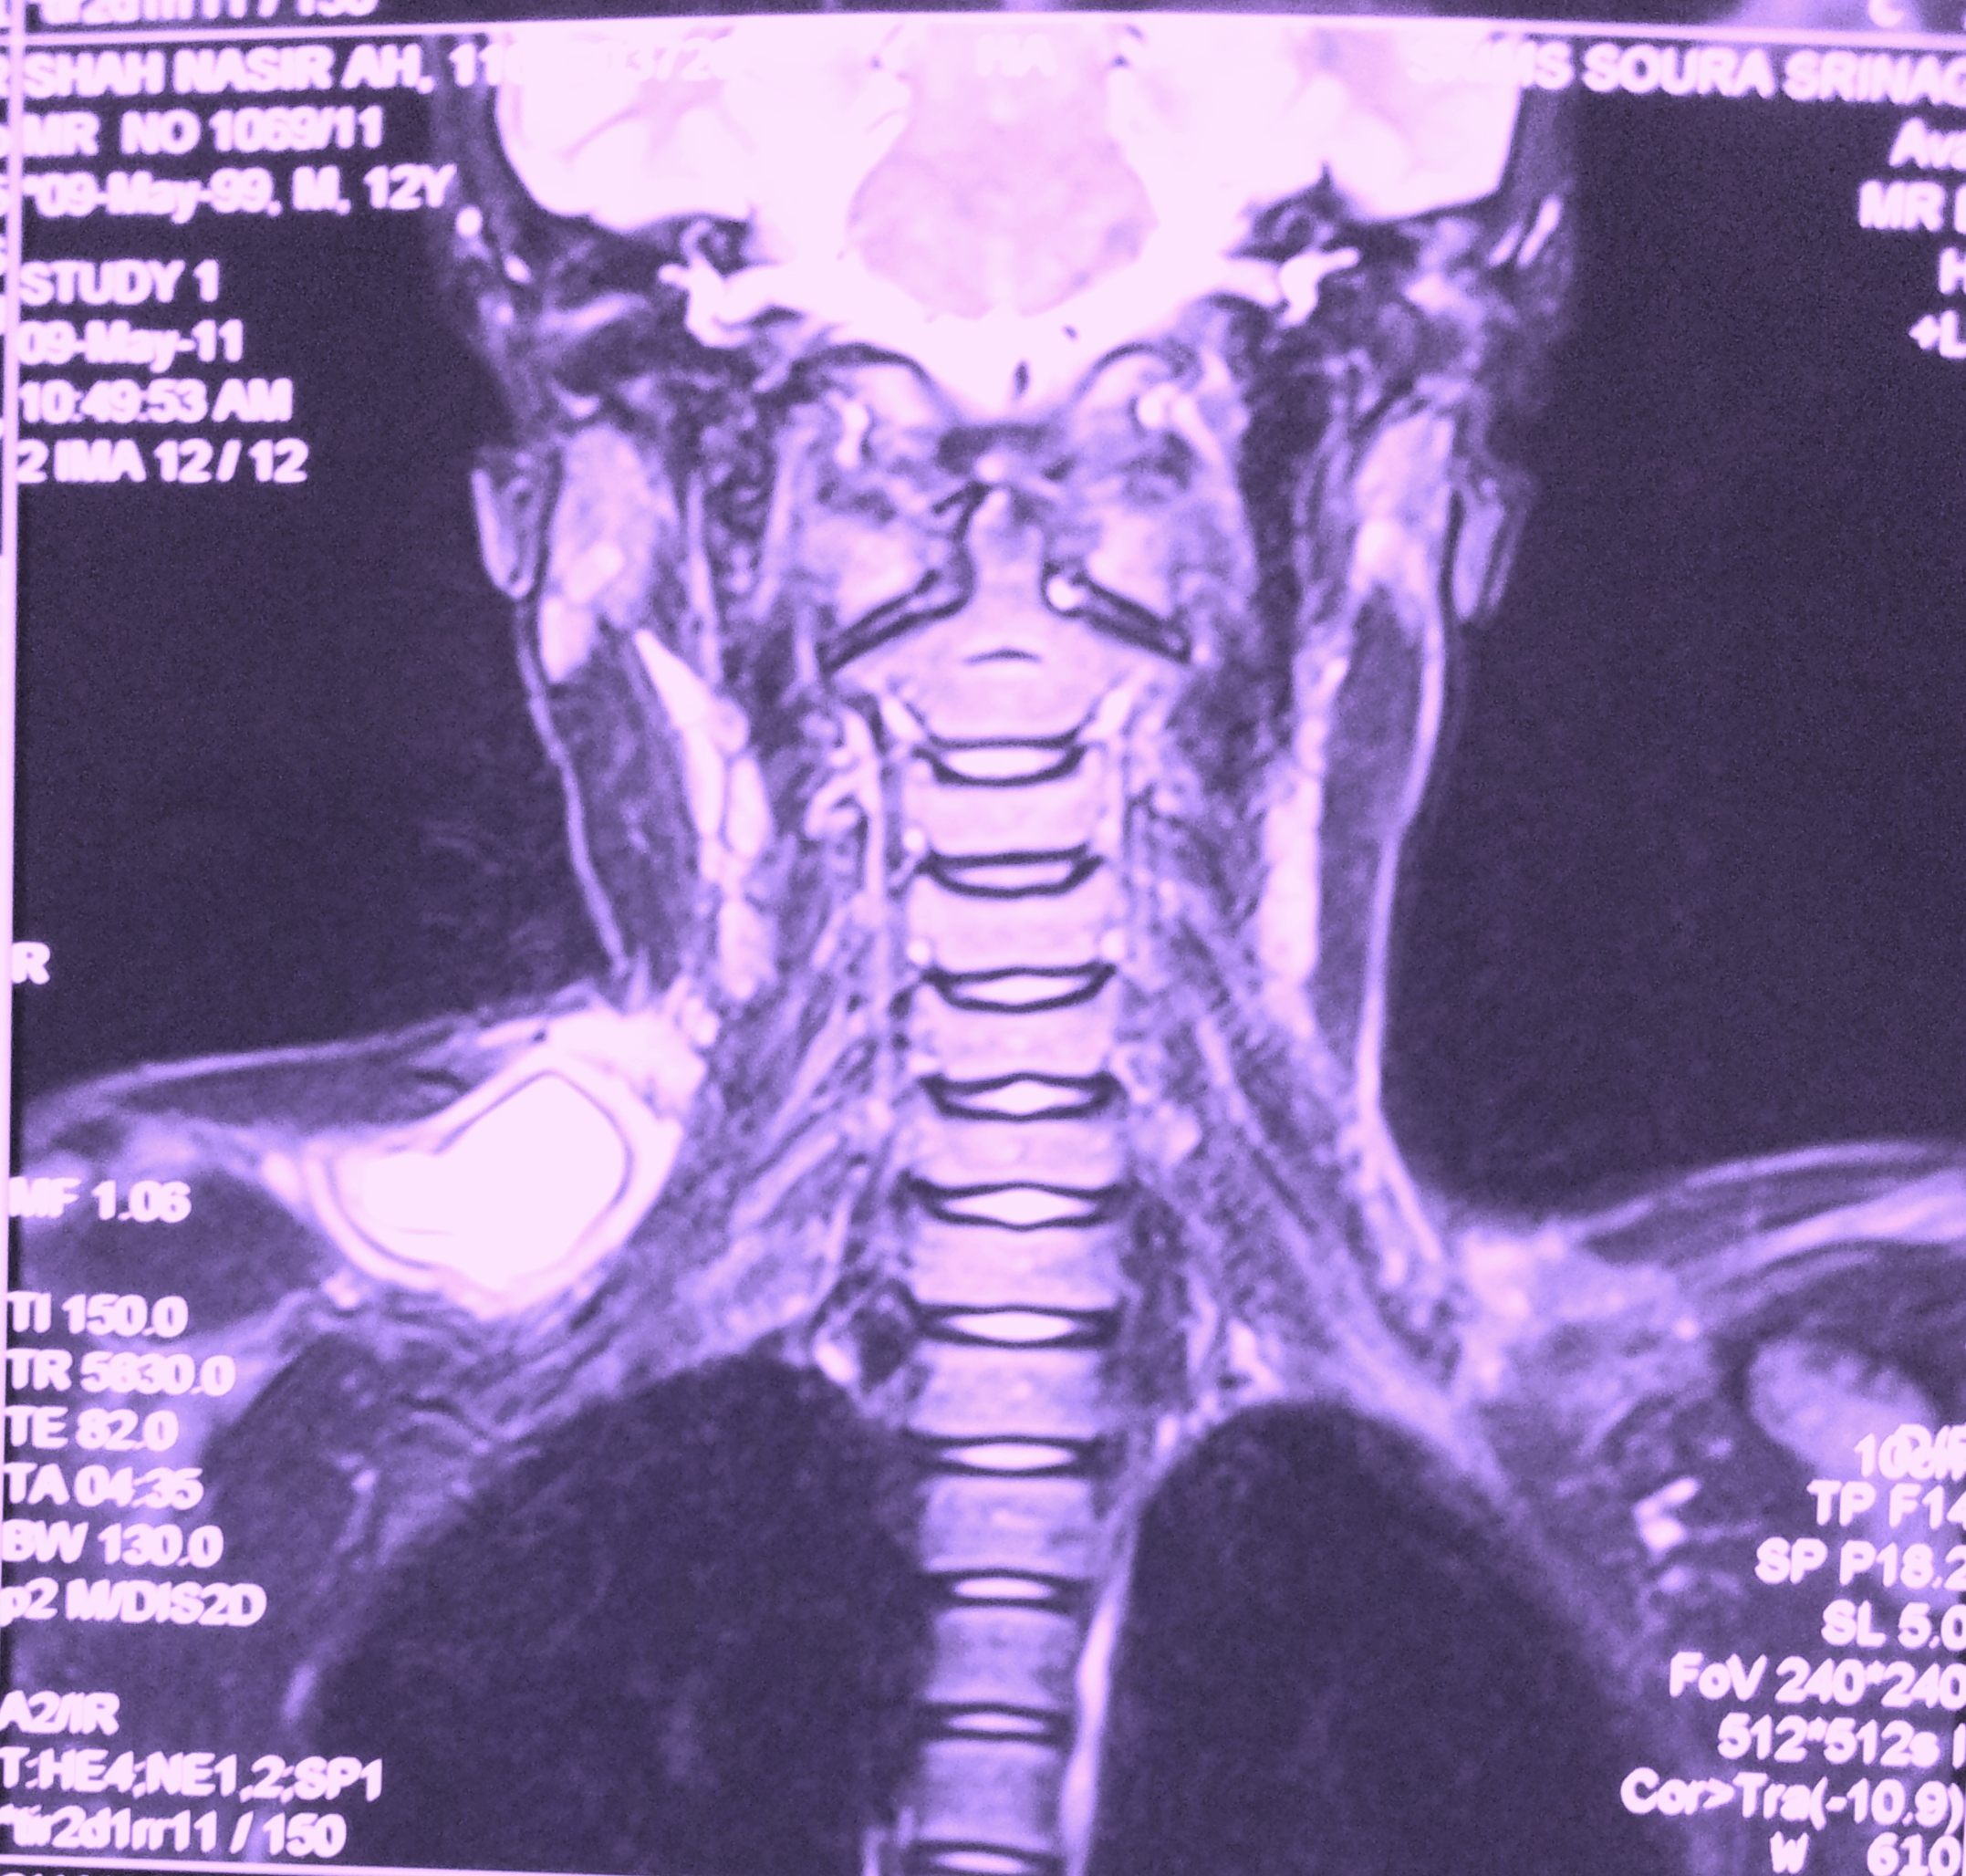

A case of hydatid cyst involving posterior triangle of neck in a 10 year old male child is reported. Diagnosis was confirmed by MRI. Surgical excision of the cyst was done. Hydatid cyst in posterior triangle should be considered one of the possibilities in evaluating a cystic swelling in this region.